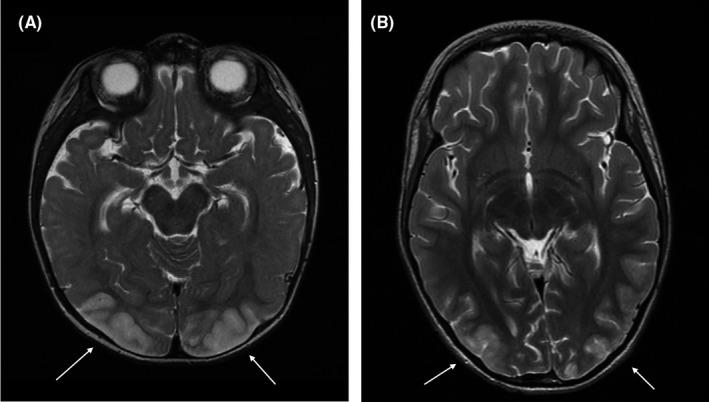

Pathophysiological aspects of posterior reversible encephalopathy syndrome in two peritoneal-dialyzed children.

Hypotension, blood pressure fluctuation, and endothelial impairment indicate possible additive pathophysiological aspects in the development of posterior reversible encephalopathy syndrome in children on peritoneal dialysis.